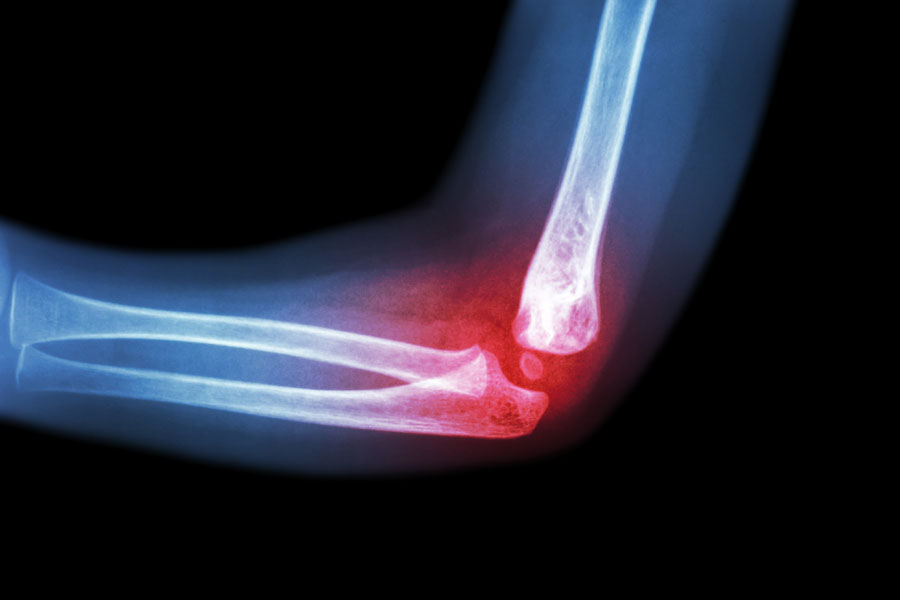

Ottobre è il mese mondiale contro l’osteoporosi e il 20 ottobre si celebra la Giornata Mondiale dell’Osteoporosi, un’occasione importante per sensibilizzare la popolazione su una patologia silenziosa ma molto diffusa. L’osteoporosi è infatti caratterizzata da una riduzione della massa ossea e da un deterioramento della sua microarchitettura, che comportano un aumento della fragilità delle ossa e, di conseguenza, un maggior rischio di fratture.

Le fratture da fragilità – in particolare quelle di femore, vertebre, polso e omero – rappresentano una delle principali complicanze dell’osteoporosi. Non solo riducono l’autonomia e la qualità di vita, ma possono avere ripercussioni importanti anche sul piano sociale e sanitario. Per questo motivo la prevenzione gioca un ruolo fondamentale.